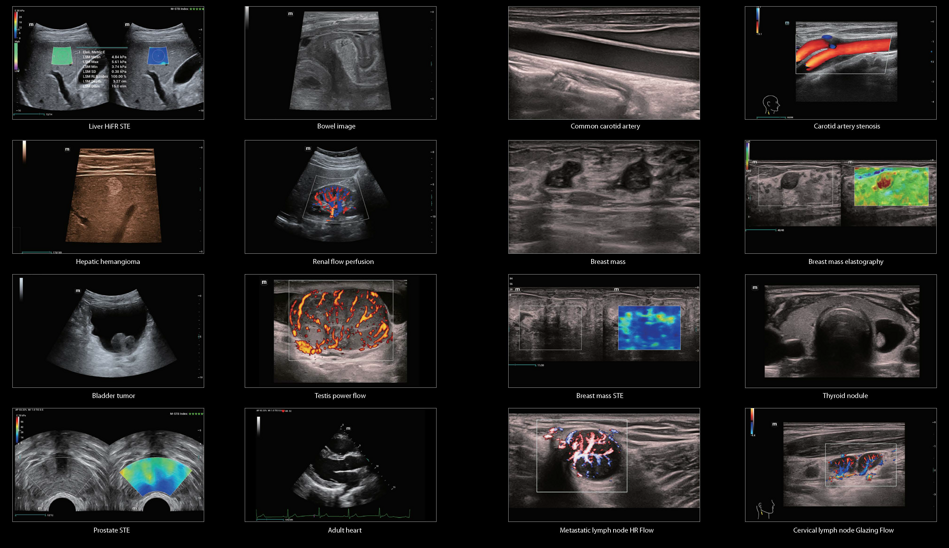

Supersonic "Aixplorer Ultimate, Mach30"

Mindray " Resona , Consona ,Portatili"

Sonoscape

Wisonic

FujiFilm Hitachi Aloka Arietta 650-750-850